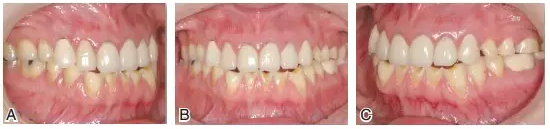

圖6患者J初診時的最大牙尖交錯位咬合情況。上頜后牙及下頜前牙區(qū)重度磨耗,后牙區(qū)牙合曲線呈上凸的倒曲線

圖7患者J初診時的下頜前伸(A)及下頜左(B)、右(C)側(cè)方運(yùn)動情況。可見在咀嚼運(yùn)動時,僅有單側(cè)上下頜前磨牙的個別點(diǎn)接觸,咀嚼效率差,咀嚼肌易疲勞